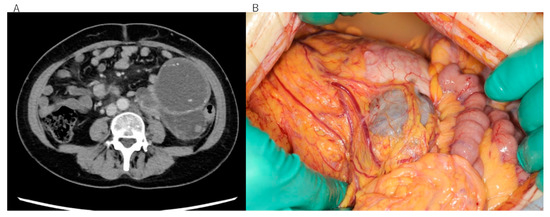

This study included two patients with EIATs, one from Seirei Hamamatsu General Hospital and one from Kobe City Medical Center Hospital. The diagnosis was malignant transformation of extragonadal endometriosis in both cases, according to criteria recommended by a Japanese survey [11]. Histologically, the tumor in patient 1 was identified as clear cell carcinoma arising in the left sigmoid colon (Figure 1A–C), whereas that of patient 2 was identified as undifferentiated carcinoma arising in the rectum (Figure 2A,B). Neither patient received hormone therapy before these cancers were diagnosed (Table 1). The patients’ characteristics are summarized in Table 1. Clinical information was obtained retrospectively from electronic medical records. The study was conducted in accordance with the tenets of the Declaration of Helsinki and Title 45 (United States Code of Federal Regulations), Part 46 (Protection of Human Subjects), effective 13 December 2001.

Figure 1.

Clinical and pathological images of the rare-site endometriosis-associated cancer (RSEAC) in patient 1. (A) Computed tomography scan showing a giant abdominal tumor. (B) Surgical findings showing RSEAC arising from the intestine. (C) Hematoxylin and eosin staining showing clear cell carcinoma.